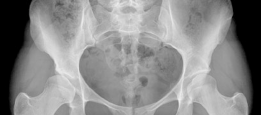

Demographics Age : 47 years Sex : Female BMI : 20.5 Relevant Past Medical History Principal pathologies : Lei…